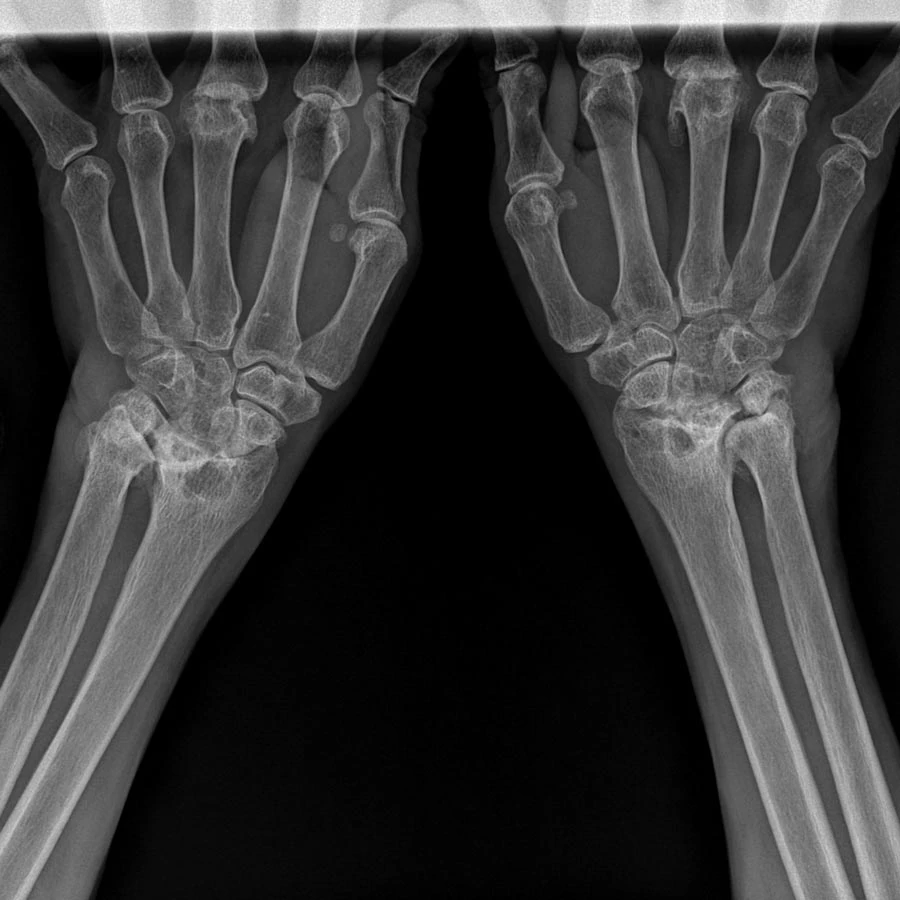

Carpal tunnel syndrome can make even the simplest movements feel frustrating and painful. Whether it’s caused by repetitive motion, poor ergonomics, or underlying nerve irritation, the pressure on the median nerve in your wrist can lead to weakness, numbness, and pain that interferes with your work, sleep, and everyday routine. But while the symptoms show up in the wrist and hand, the root cause often traces back to spinal misalignment or nerve interference in the neck and upper back.

The median nerve – which is compressed in carpal tunnel syndrome – originates in the neck and travels all the way down the arm. Misalignments in the cervical spine can contribute to or mimic carpal tunnel symptoms.